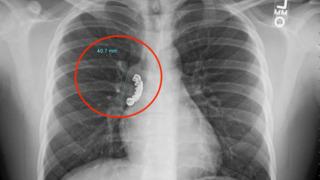

Halk arasında sara hastalığı olarak da bilinen epilepsi, beyin hücrelerinde oluşan etkileşimin bozulmasıyla ortaya çıkmaktadır. Beyin fonksiyonlarında hasar oluşmasıyla kişide meydana gelen bir kronik rahatsızlık olup, nöbetler halinde kendini belli eder. Nöbet süresi yaklaşık 30 saniye-2 dakikadır. 5 dakikadan daha uzun süren nöbetler için tıbbi yardım alınması gerekmektedir. Epilepsi hastalığının genetik olması mümkün bir durum olup anneden çocuğa geçmesi olağan bir durumdur. Vücut üzerindeki ani kasılmalar, şuur kaybı, sabit bir noktaya bakmak,seri bir şekilde baş sallama, korku ve hızla göz kırpmak gibi durumlarda kişinin epilepsi nöbeti geçirdiği anlaşılır. Epilepsi nöbeti geçiren hasta yan yatırılır ve etrafı boş bırakılarak rahat nefes alması sağlanır.